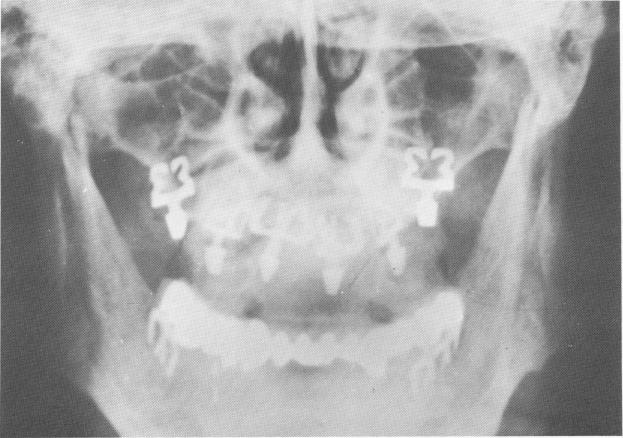

Fig. 11-205. Blades may be set at any angle in the arch to take advantage of the bony landscape. The posterior blades in the maxillae were set buccopalatally in the tuberosities. The remaining blades in both arches were inserted mesiodistally, with their broad faces lying in line with the curvature of the arch.

2 Posterior blades in maxillae set buccopalatally in tuberosities